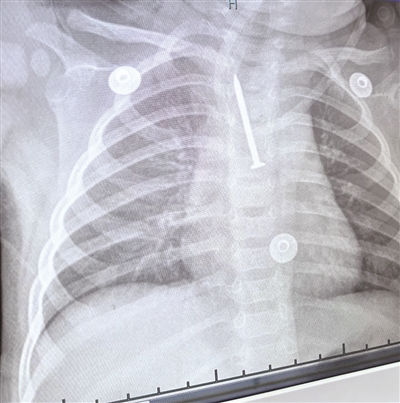

见惯了各类异物的放射科医生,在看到X片结果时,也吓了一跳。“情况特殊,孩子年龄小,难配合,任何哭闹或呛咳都可能导致钉子移位,进而引发气管和神经损伤。”

“这枚铁钉太长,正好斜跨在气管和气管分叉的气管隆突之间。”呼吸内科医生侯进飞介绍,铁钉大部分钉体位于气管内,尖端朝上,紧贴气管壁,末端朝下,落在隆突和左侧支气管之间。孩子的每一声哭吵甚至咳嗽,都有可能造成尖端扎破气管壁引起气胸、纵隔气肿甚至划破气管周围伴行的大血管引起大出血。

更麻烦的是,术前复查的胸片显示铁钉的位置比在当地医院拍片时更深了,说明异物还在下移!